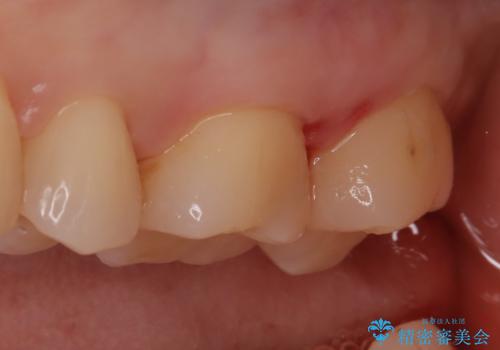

【セラミックインレー】適合の良いセラミックインレーを入れたい。

- 毎回フロスが引っかかることを気にされており、改善のため適合の良いセラミックインレーで修復しました。

以前に他院で詰め物をいれた時は、フロスが毎回ちぎれて大変だったそうですが改善して喜んでおられました。

当院のセラミックインレーは必ずラバーダムを使用して接着しています。